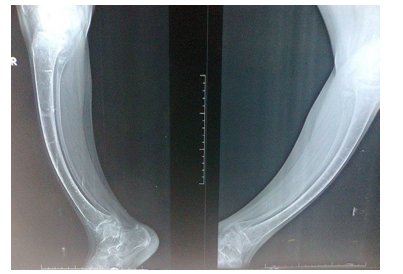

The younger sister laboratory tests performed during May, 2023 showed normal serum calcium of 9 mg/dL and normal serum phosphorus of 5.16 mg/dL. However, the alkaline phosphatase was high at 164 u/l (Normally less than 140 u/l). Old radiographs of the older sister showed osteopenia, fracture in the upper limb, and progressive bowing with no rachitic changes. Figure-2A and B shows a lower limb radiographs taken during December, 2019. Later radiographs showed more severe bowing (Figure-2C).

Old radiographs of the younger sister showed osteopenia, fracture in the upper limb, and progressive bowing with no rachitic changes. Figure-3A and 3B show lower limb radiographs showing progressive bowing. Figure-4 (A, B, C, and D) show recent bone radiographs of the younger sister taken during May, 2023 which showed osteopenia, bowing with no rachitic changes. Radiograph of the pelvis showed mild protrusio acetabula (Figure-4A). Radiograph of the wrist showed no rachitic changes (Figure-4B). Radiograph of the lower limbs showed bowing, cortical thinning with scanty spongiosa (Figure- 4C). Lateral skull radiographs showed platybasia (Figure-4D).

Figure-2C: Radiographs showed more severe bowing

Figure-3A: lower limb radiograph showing progressive bowing

Figure-3B: lower limb radiograph showing progressive bowing